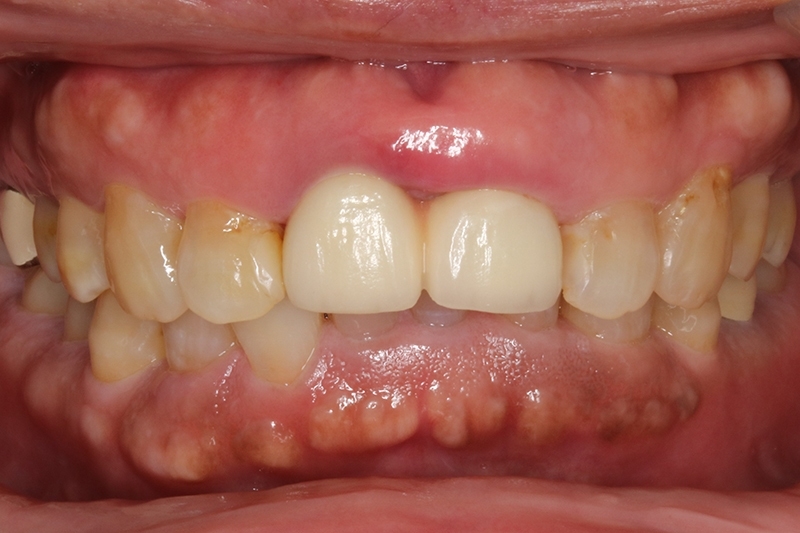

門牙植牙全瓷冠+側門牙全瓷冠完成照

術前術後對照圖

術後